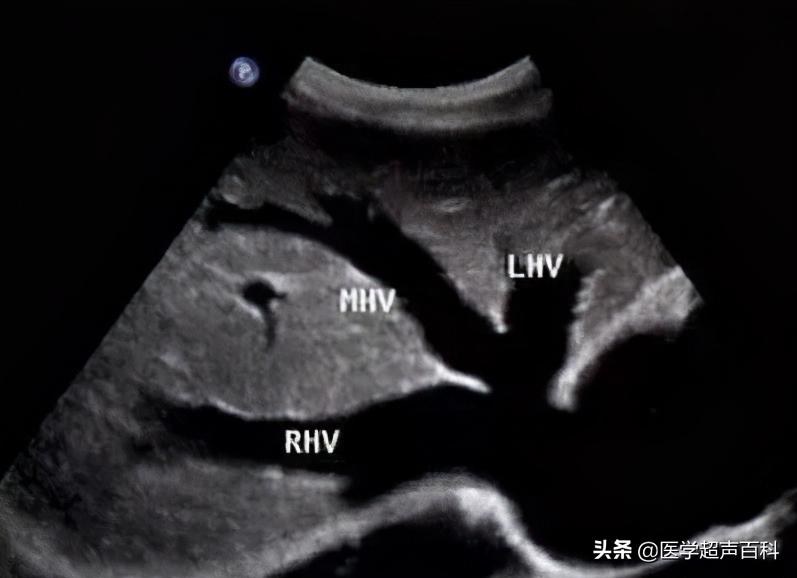

2.三支肝静脉扩张,直径达0.8-2.0cm,呈明显增粗的无回声管腔,各级分支均易清晰显示,扩张的肝静脉在第二肝门呈花瓣样进入下腔静脉。有时腔内见血细胞缓慢的流动,收缩期由右房反流,逆向肝静脉。